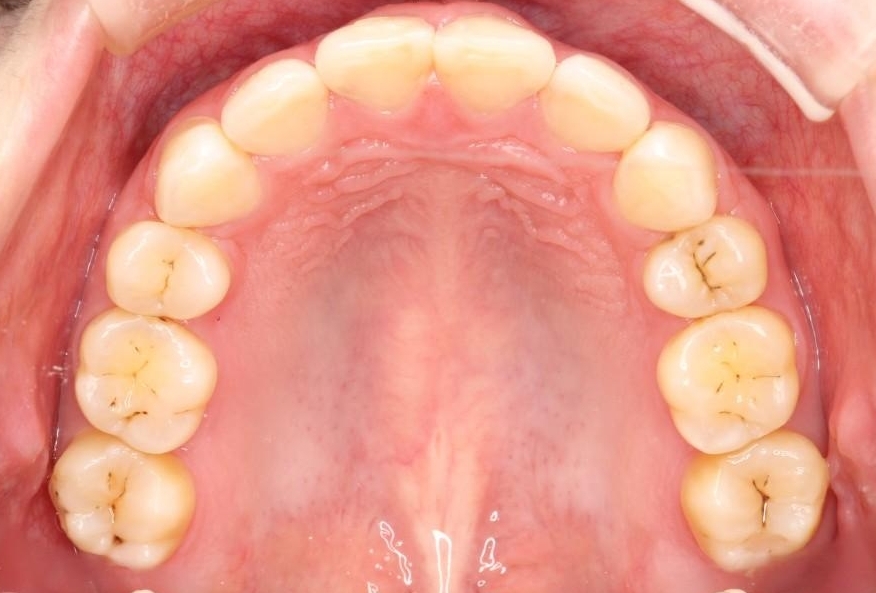

【20代女性】出っ歯の矯正 治療例

口元が出ていることを気にされて来院されました。

治療費の安い矯正治療を希望されていたため、メタルのワイヤー装置にて治療する計画にしました。また、歯みがきが苦手だったため、矯正治療をする前に徹底的にブラッシング指導を行いました。

出ている歯を引っ込めるためのスペースを作るため、上下左右の小臼歯を抜歯し、ワイヤー矯正を行いました。治療後は、口元がスッキリとしたことで患者様にも喜んでいいただきました。